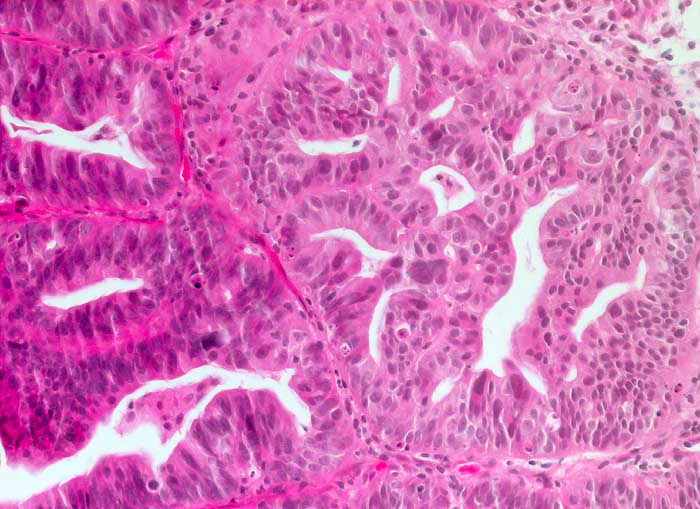

Hoch differenziertes endometrioides Karzinom

Das Karzinom bildet komplexe kribriforme Strukturen, aber keine soliden Tumorkomplexe. Die Zellatypien sind leicht bis mässig ausgeprägt. Wie in der Zytologie (ID6220) sieht man auch histologisch einzelne sehr grosse Kerne.

Zytologische Diagnose: Nicht klassifizierbare Zylinderepithelien, eher maligne.

Hochaufgebautes Endometrium

200